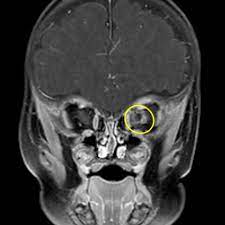

Morning Glory Syndrome Eye Radiology Reference Article Radiopaedia Org

The brightly colored trumpet-shaped flowers have a slight fragrance and are popular with butterflies and hummingbirds. 6205 Kate Road Monroe NC 28110. Morning glory disc anomaly is characterised by an enlarged funnel-shaped excavation in the optic disc with peripapillary chorioretinal pigmentary changes and overlying central white glial tuft.